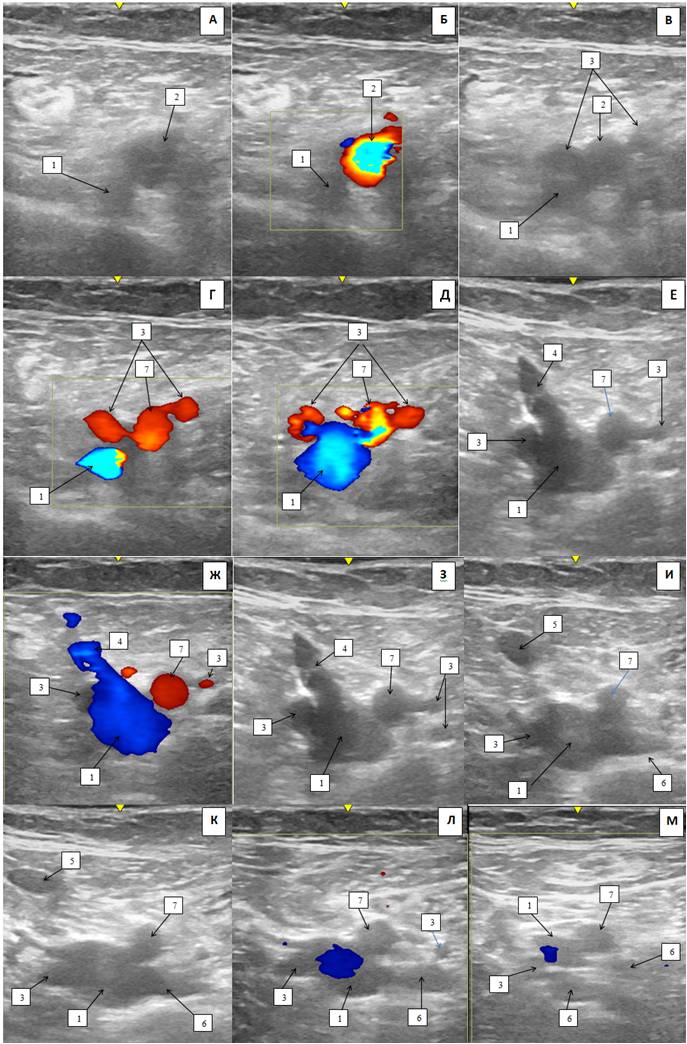

Справа: ГАБ представлена двумя стволами, которые отходят от латеральной и задней поверхностей ОБА. ОБВ выше уровня СФС представлена одним стволом, ниже уровня СФС представлена двумя стволами, расположенными между одним из стволов ГАБ, который отходит от задней поверхности ОБА. В латеральный ствол ОБВ впадает ГВБ. На уровне впадения ГВБ, медиальный и латеральный ствол ОБВ соединяются между собой коммуникантной ветвью. Дистальнее этого уровня медиальный ствол ОБВ сопровождает ГАБ, отходящую от задней поверхности ОБА. Латеральный ствол ОБВ сопровождает ПБА (рис. 3, 4).

Рис. 3. Ультразвуковая дуплексная сканограмма сосудов верхней трети бедра справа пациентки К. (двухмерный, серошкальный режим (В-режим) и режим цветового допплеровского картирования; поперечный срез): А–Б — выше уровня сафенофеморального соустья; В — уровень сафенофеморального соустья; Г–Н — ниже уровня сафенофеморального соустья.

Примечания: 1 — общая бедренная вена, 2 — общая бедренная артерия, 3 — глубокая артерия бедра, 4 — сафенофеморальное соустье, 5 — большая подкожная вена, 6 — глубокая вена бедра, 7 — поверхностная бедренная артерия, 8 — анастомоз между общей бедренной веной, 9 — бедренная вена.